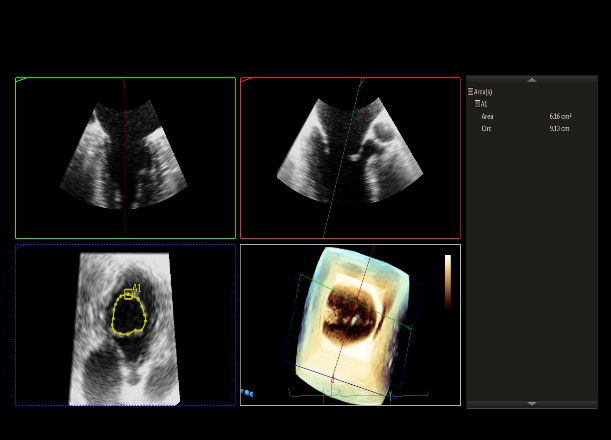

术前超声评估

术前超声诊断

LVOT-color:MR(重度),返流面积11.3cm2

肺静脉血流频谱呈收缩期反向

3D-color MV view:血流主要来源于2、3区

Qlab软件勾画估测瓣口面积约:6.16cm2

TEE LVOT切面返流量评估

TEE 4-Ch view返流量评估